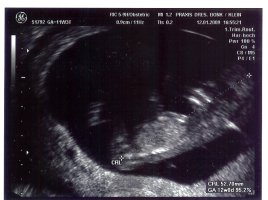

achso, wir waren übrigens WE bei der family u.a. auch bei meiner mum und da haben wir wieder bilder eingescannt....

• SSW 12.jpg

SSW 12.jpg

175,1 KB · Aufrufe: 371